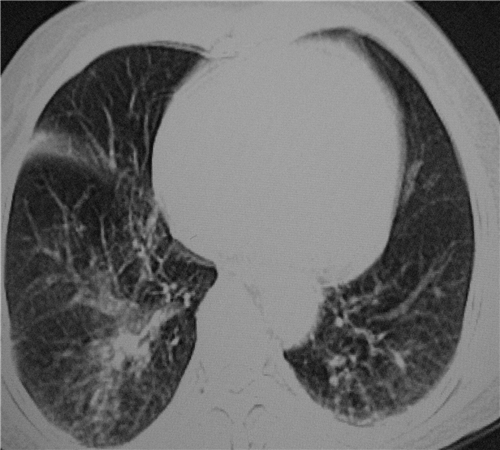

标题: CT26849:女67岁反复胸痛两天余,临床考虑夹层。 [打印本页]

标题: CT26849:女67岁反复胸痛两天余,临床考虑夹层。

双下肺感染,右侧显著。有无夹层,增强扫描后再诊断。

1.考虑双肺感染,右侧为重;2.建议ct增强或mri排除主动脉夹层

双下肺感染,右侧显著。有无夹层,增强扫描后再诊断。食道未见异常。

平扫未见确切夹层征,建议必要时增强扫描或mri检查。